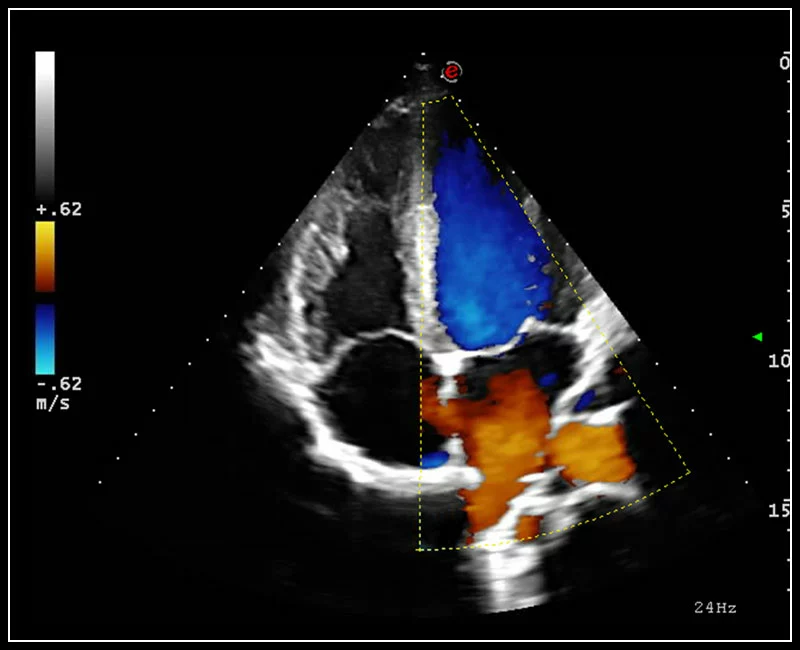

Q7 - Cardio CFM

Q7 - Cardio CFM